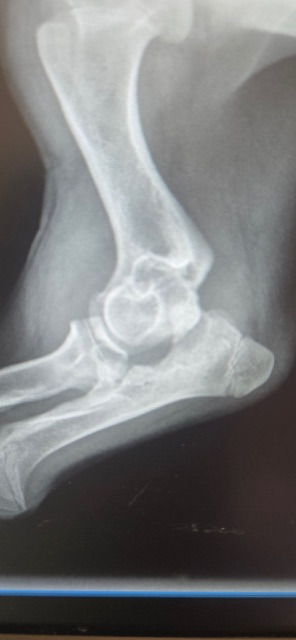

When we took her to the vet (a few days after the “adoption”) and after the examination and new x-rays, we were told that Ashlyn in fact has elbow dysplasia - a genetic/hereditary condition. We were immediately referred to an orthopedic vet and had a consultation. During the consultation, we learned that as the elbow dysplasia was not discovered nor treated earlier, it would require a full replacement of the joint as her growth plates were closing. We also learned that due to this untreated condition, she is not growing properly and it is very painful. The quote for the surgery came in at $7,117.94, which does not include the physical therapy, wound care or removal of the external screws, which is an estimated additional $2,000.